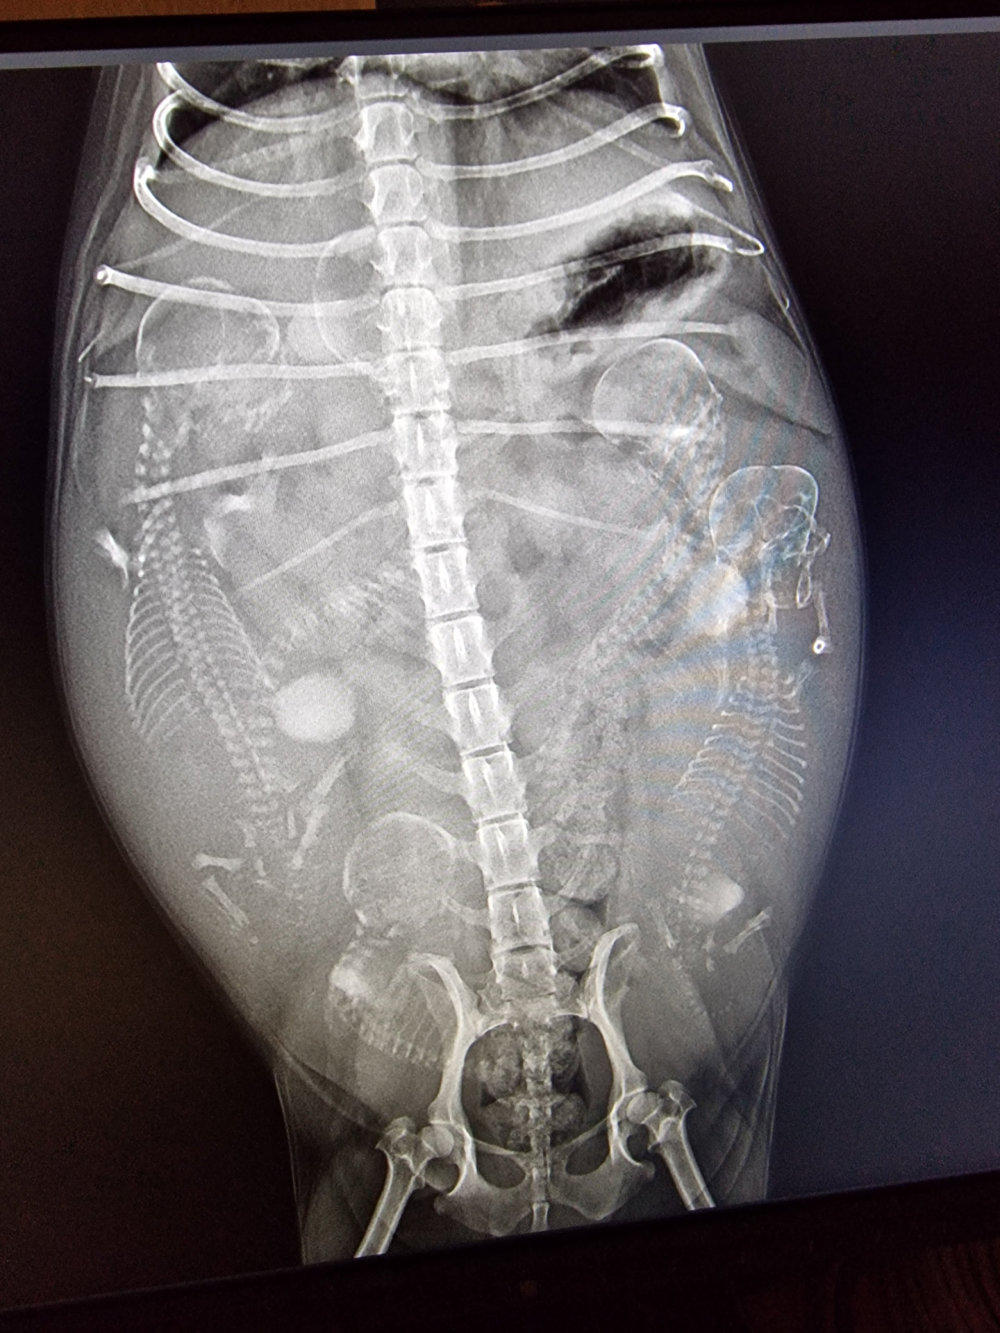

So, heute Morgen war unser Frauli auch mit den anderen drei Mädels zum Röntgen. Im Laufe der nächsten Woche kommt richtig Leben in unsere Bude. Hi, hi. (Röntgenbilder Yule, Lotta und Gina v.l.n.r.) Yule´s Welpen-Nestchen steht auch. Die von Lotta und Gina bauen unsere Niefi´s am Wochenende auf.

Weitere 4 Wochen sind vergangen und unser Frauli war mit Mala bei unserer Tierärztin „Baby‘s gucken“. Wir hatten es ja schon fast vermutet, da sie nur noch durch die Gegend walzt und wir sie seit gut einer Woche auch die Treppe rauf- und runter tragen. „Die Hütte ist voll!!!“ Grins. Könnt ihr die Zwergis zählen? Alles ist für die Geburt vorbereitet. Unser Frauli sagt ja, „es werden Sonntagsbabys“. Mal schauen, ob sie Recht behält. Wir melden uns wieder, sobald unsere Kühchen „auf der Weide grasen“. Smile.